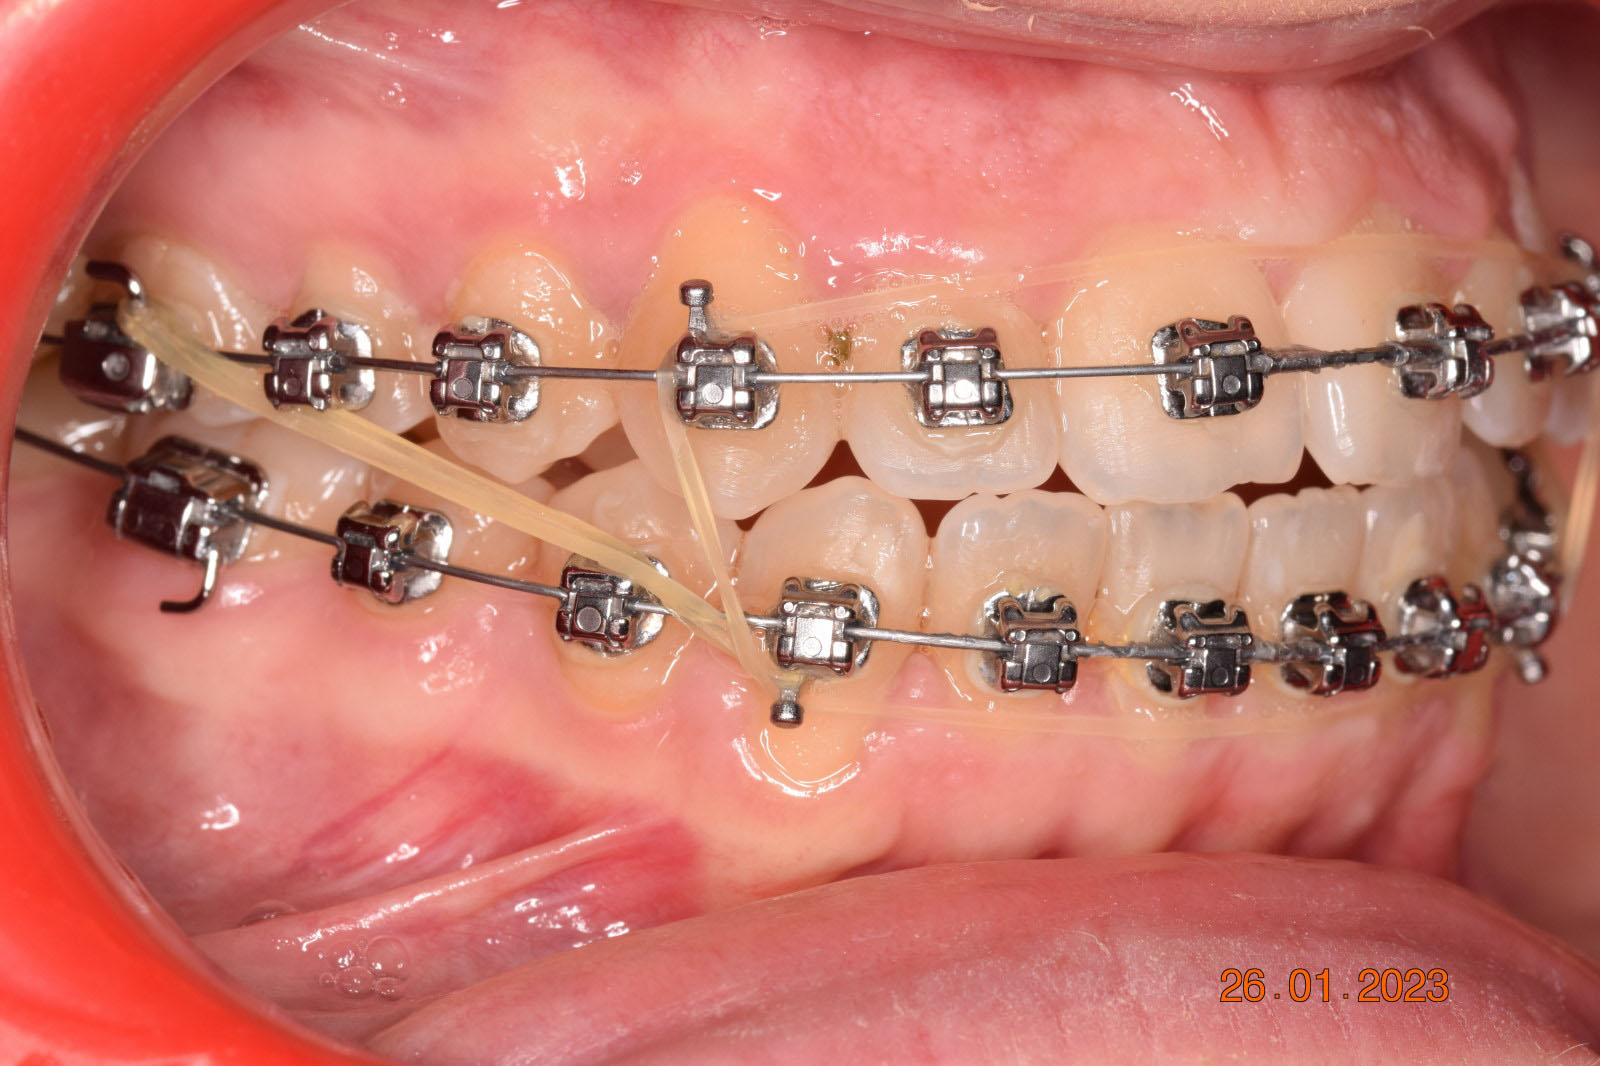

The treatment began in 2017. Given the patient’s preference for less visible brackets, Damon Clear brackets were selected. High torque upper cuspids and low torque upper incisors were chosen to offer the best torque control for upper arch development. For the lower arch, there were no alternative bracket configurations available. Bite turbos were applied to the upper second molars.

The results were unsatisfactory and the patient began losing interest in the treatment. Dr. Coca and the patient agreed to extend the treatment for six more months and then stop, regardless of the outcome.

This case posed challenges in all three spatial dimensions, compounded by significant crowding. The patient was highly compliant and maintained excellent oral hygiene throughout the 5.5 years of treatment, which required more than 30 clinical appointments.